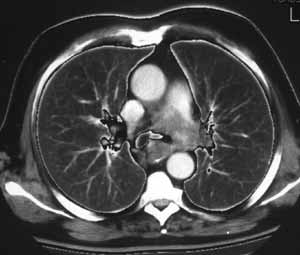

Рис. 3. КТА легочных артерий. Центральный рак легкого. Дефект контрастирования ствола и левой легочной артерии вследствие инвазии опухолью.